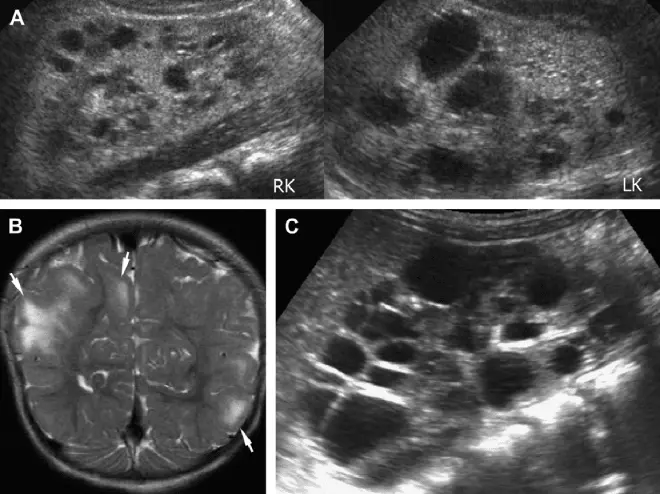

Как уже говорилось ранее, кистозные тела в почках часто не проявляют симптомов на первых стадиях развития. Диагностировать аномальное тело в почках можно при УЗ-исследовании организма или рентген-диагностике. Прямыми признаками дисфункций и нарушений работы мочеполовой системы можно считать периодические боли в пояснице или животе, покалывания в боку, перепады артериального давления, а также частые недомогания, проблемы и боли при мочеиспускании. В зависимости от типа и формы кисты в почке МКБ 10, а также места ее расположения, больной человек может замечать наличие гноя или крови в моче, испытывать режущие или тянущие боли под ребрами, испытывать боли при мочеиспускании.